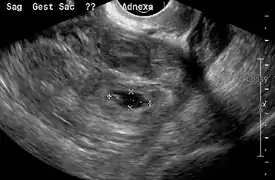

An ultrasound showing a gestational sac with fetal heart in the fallopian tube has a very high specificity of ectopic pregnancy. It involves a long, thin transducer, covered with the conducting gel and a plastic/latex sheath and inserted into the vagina.[32] Transvaginal ultrasonography has a sensitivity of at least 90% for ectopic pregnancy.[5] The diagnostic ultrasonographic finding in ectopic pregnancy is an adnexal mass that moves separately from the ovary. In around 60% of cases, it is an inhomogeneous or a noncystic adnexal mass sometimes known as the "blob sign". It is generally spherical, but a more tubular appearance may be seen in case of hematosalpinx. This sign has been estimated to have a sensitivity of 84% and specificity of 99% in diagnosing ectopic pregnancy.[5] In the study estimating these values, the blob sign had a positive predictive value of 96% and a negative predictive value of 95%.[5] The visualization of an empty extrauterine gestational sac is sometimes known as the "bagel sign", and is present in around 20% of cases.[5] In another 20% of cases, there is visualization of a gestational sac containing a yolk sac or an embryo.[5] Ectopic pregnancies where there is visualization of cardiac activity are sometimes termed "viable ectopic".[5]

Transvaginal ultrasonography of an ectopic pregnancy, showing the field of view in the following image.

Ultrasound image showing an ectopic pregnancy where a gestational sac and fetus has been formed.